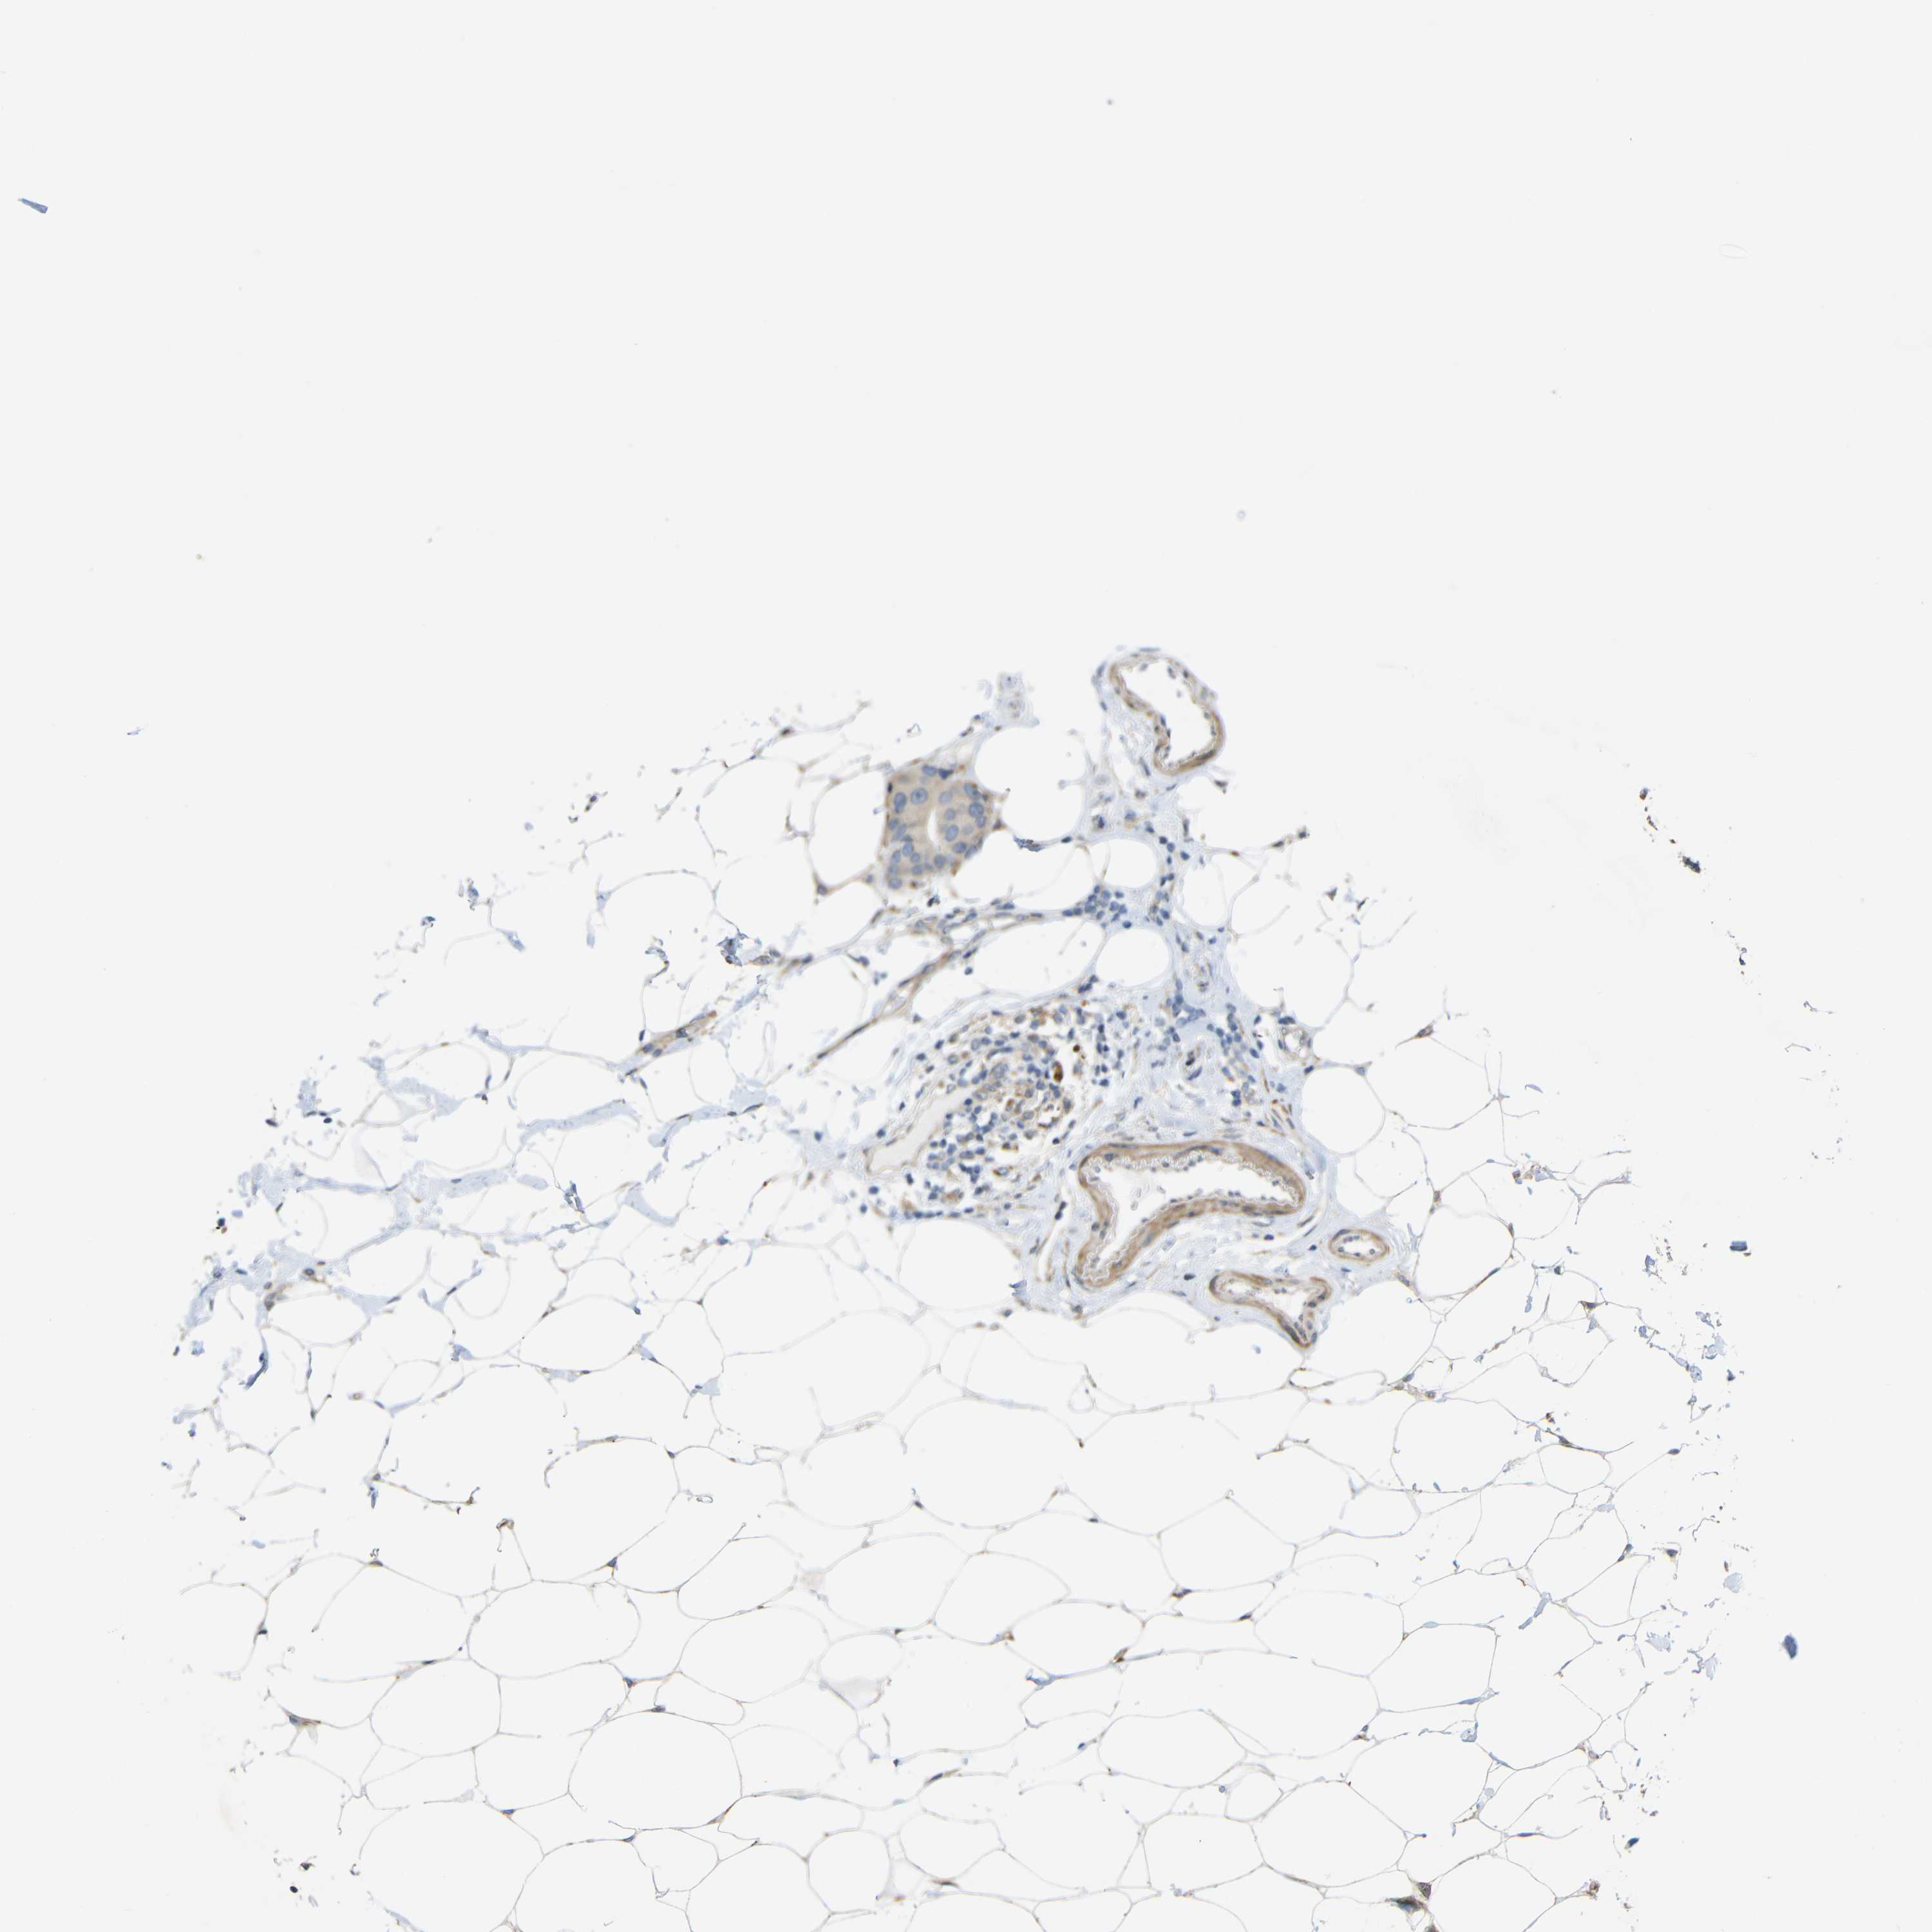

CANCER BREAST CANCER Show tissue menu

BRCA TCGA BRCA VALIDATION PROTEIN EXPRESSION